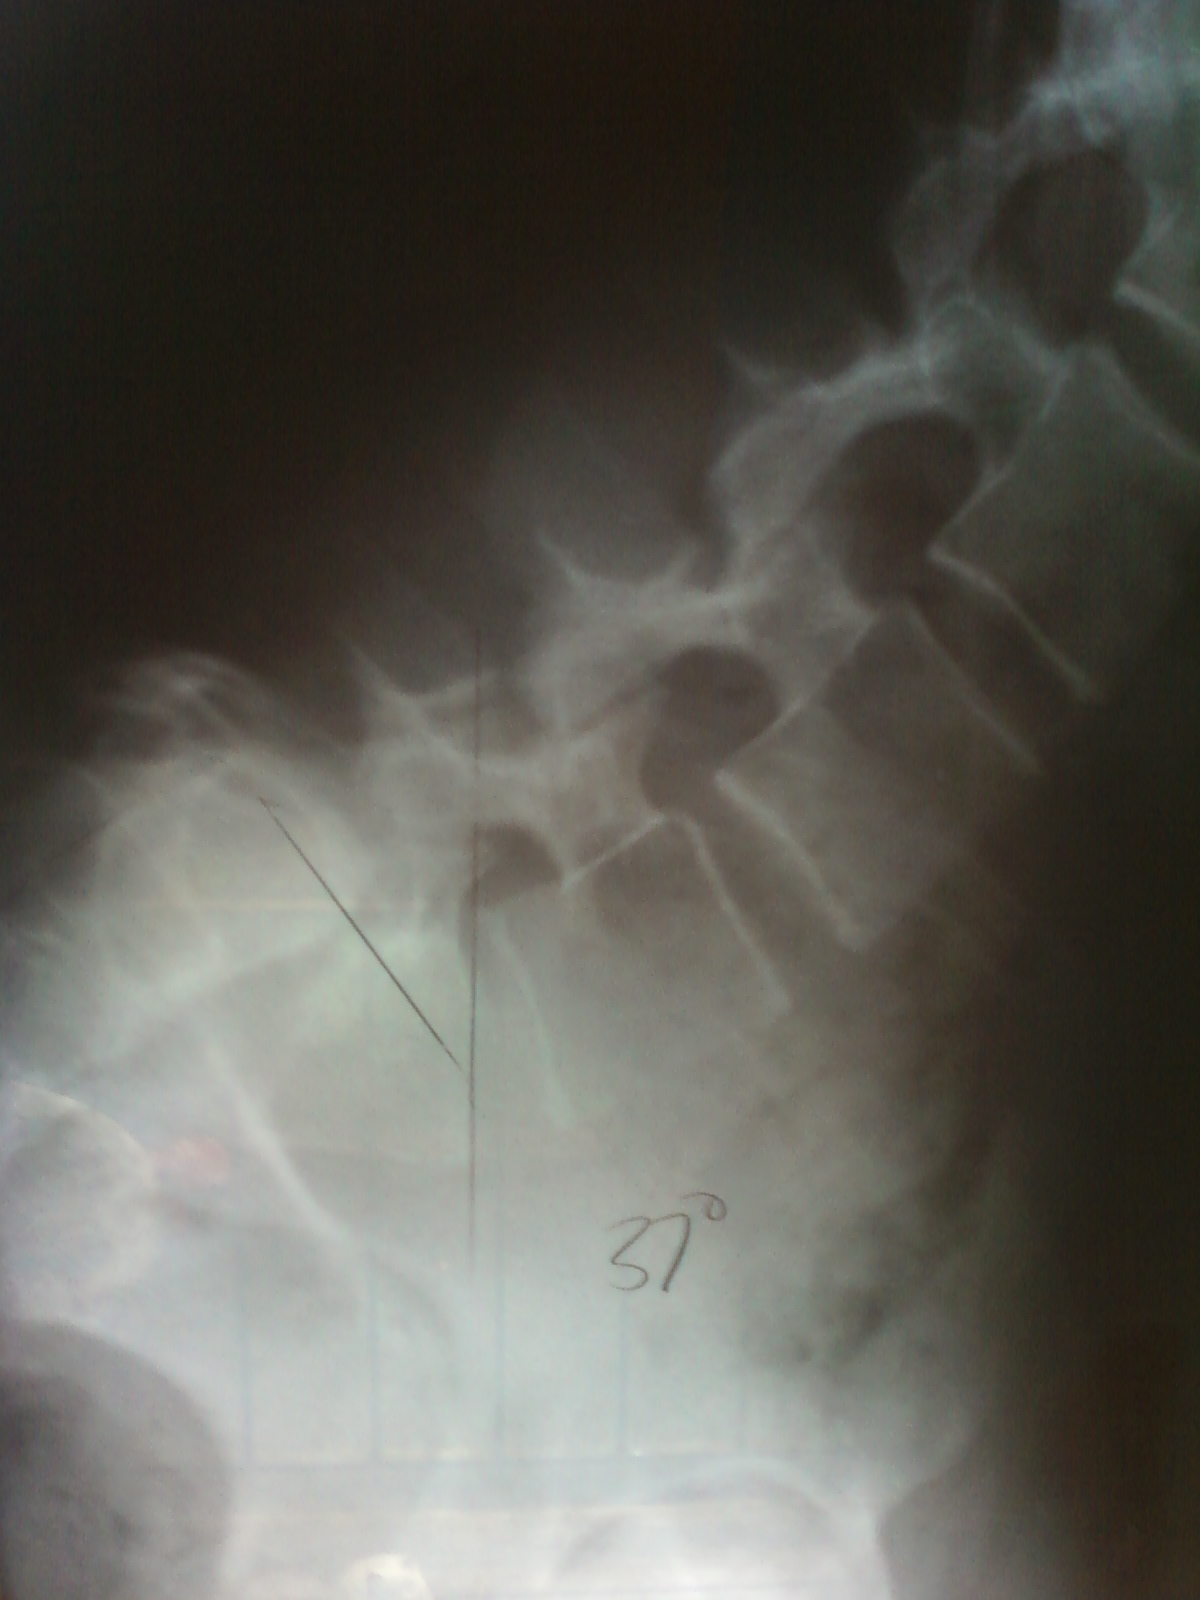

Pre & Post Operative X-Rays (From my 1997 surgeries & body traction)

Pre-Operative 1997 - Complete slip called Spondyloptosis

Post-Operative 1997. After full body traction, which increased my height by 3 inches, but L5/S1 still sits at a grade 5 Spondylolisthesis.